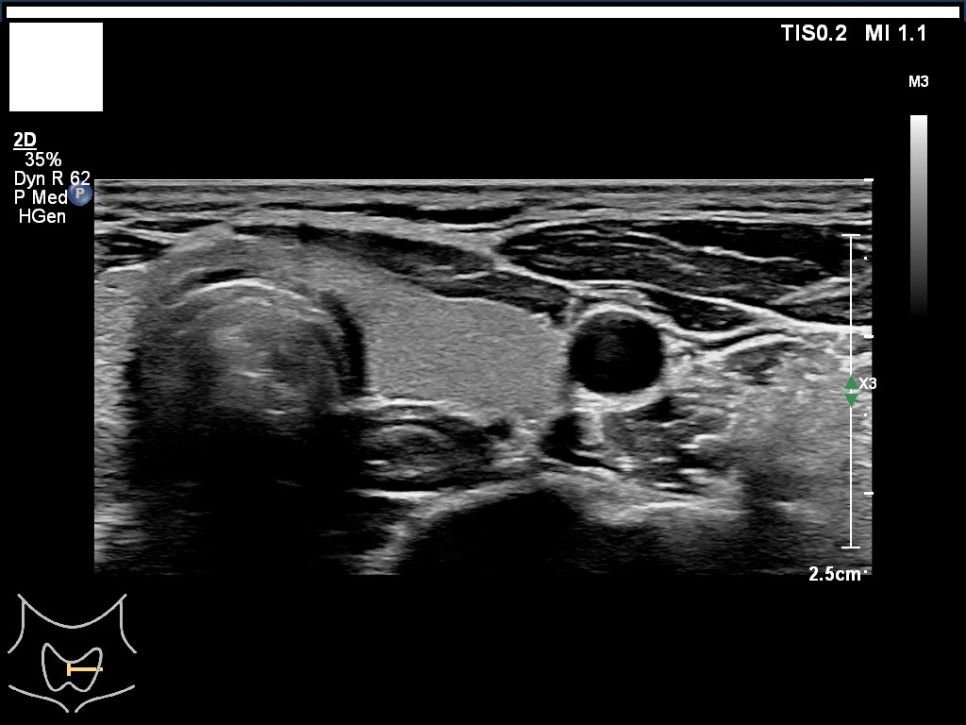

갑상선, 부갑상선 초음파 검사 급여 기준 1. 표준 영상의 범위 모든 영상에는 경부의 해부학적 위치(모식도나 문자)를 표기하여야 한다.

A) 병변이 없는 경우: 우엽 중부 가로 스캔, 우엽 중앙부 세로 스캔, 협부 가로 스캔, 좌엽 중부 가로 스캔, 좌엽 중앙부 세로 스캔, 우경부 림프절, 좌경부 림프절 나) 병변이 있는 경우: 병변이 없는 경우의 표준 영상과 함께 병변 부위에서 2개의 수직 관계 단면 영상(횡단/종단) 및 병변의 크기가 측정된 경우: 병변이 없는 경우의 표준 영상

좌측 경부 림프절 / 중심 경부 림프절 / 협부 옆 스캔 2. 판독 소견서가) 등록 번호, 성명, 생년월일 또는 연령, 성별, 검사명, 검사 일시, 판독 일시, 검사와 판독한 의사(면허 번호), 의료기관명, 검사 소견 및 결론 나) 검사 소견에는 갑상선 에코, 병변의 유무를 기술하여야 한다. 결절이 있을 경우 위치, 최대지름, 주요 소견, K-TIRADS의 내용을 기술하여야 하며, 암으로 진단된 결절을 추적할 경우 위치, 3방향 직경, 주요 소견, 전 검사와 변화 여부, 경부 림프절의 평가 및 이상 소견 여부를 기술하여야 하며, 경부 림프절에 이상이 있을 경우 위치, 크기, 주요 소견을 기술하여야 한다. 결절이 여러 개 있을 경우 암 위험도에 따라 선택적으로 기술할 수 있다. 또 소아 등에서의 환자의 협력도 음창 등이 좋지 않아 표준 영상 획득에 제한이 있는 경우 추가 기술해야 한다.